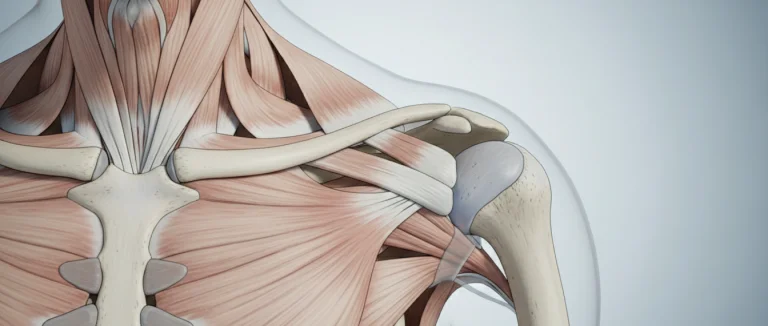

Сухожилие надостной мышцы входит в состав вращательной манжеты, обеспечивая отведение руки и стабилизацию плечевого сустава. Основные факторы риска включают:

Разрыв сухожилия надостной мышцы — одна из самых распространённых травм вращательной манжеты плеча, требующая своевременного лечения разрыва сухожилия надостной мышцы. При отсутствии адекватного вмешательства пациенты сталкиваются с хронической болью, ограничением подвижности и снижением качества жизни. По данным международных исследований, более 30 % пациентов с разрывом сухожилия надостной мышцы нуждаются в оперативном вмешательстве в течение первого года после травмы.